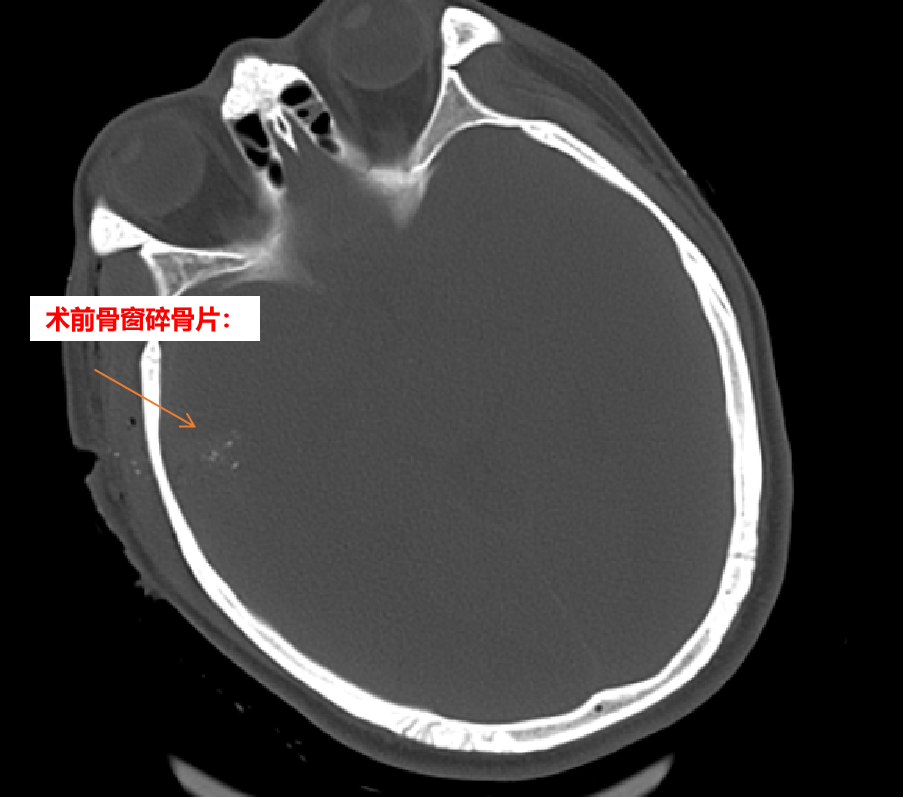

患者张某平,男,41岁,因“重型颅脑爆炸伤”于2021年10月10日收入兰陵县人民医院颅脑创伤外科进行抢救。一颗子弹自患者右侧颞部击碎颅骨进入脑内约15cm,造成多个颅骨碎骨片进入脑内,并造成弹道内的峰脑内血肿,医护人员在充分术前准备下立即行开颅血肿清除异物和脑内血肿手术。

术中见右颞骨一0.5*0.5cm大小的洞口,用铣刀做出约10*6cm大小骨瓣,取下骨瓣后见右颞叶表层一1*1cm大小洞口,沿洞口进入,清除多枚碎骨片及脑内血肿,并仔细止血,放置引流管一枚,术毕回病房。